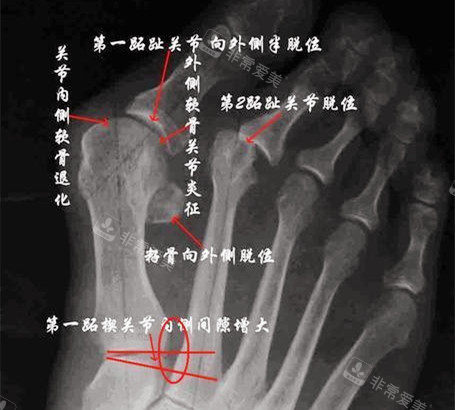

怀着紧张又期待的心情,我来到了韩国的整形医院。医院的环境非常舒适,工作人员也都非常热情和正规。在面诊时,医生仔细地检查了我的脚部情况,用正规的仪器进行了详细的测量和分析。

医生根据我的具体情况,制定了个性化的手术方案。他耐心地向我解释了手术的过程、风险和术后注意事项,让我对手术有了更多方面的了解。我也向医生提出了自己的疑问和担忧,医生都一一进行了解答,让我心里踏实了许多。